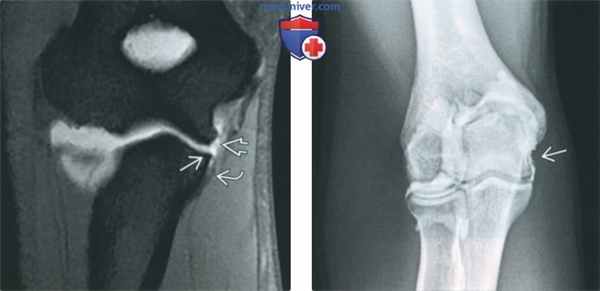

(Слева) МР-артрография в режиме Т1ВИ FS, коронарный срез: визуализируется поверхностный разрыв ЛоКС. Связка отделилась от возвышенного бугорка, но дистальнее осталась прикрепленной. Такая картина получила название симптома «Т». Проксимальный отдел связки неравномерно истончен.

(Справа) Артрография, передне-задняя проекция: отмечается неровный контур ЛоКС, соответствующий ее поверхностному разрыву.